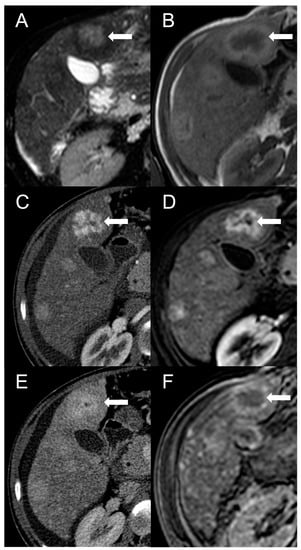

Finally, in BCS is possible to encounter pseudo-lesions. A typical example is the selective hypertrophy of the caudate segment (or any other segments with preserved venous drainage) in chronic BCS, which may take a tumor-like appearance (Figure 8) [50]. The hypertrophied segments may be hyperdense on unenhanced CT scan or exhibit T1-hyperintensity and mild T2-hypointensity in MRI with elevated restriction in DWI due to increased cellularity. The hypertrophy-induced pseudo-lesions usually display the regular enhancement pattern observed in normal liver, but this can be misleading in cases of extensive perfusion alterations due to venous congestion or in advanced stages of the disease. A useful clue for the differential diagnosis is the identification of normal, non-distorted intrahepatic vessels within the hypertrophied segment. Perfusion-associated pseudo-lesions can also occur, especially in acute or subacute BCS with proximal venous obstruction [51]. After contrast agent administration, areas of venous congestion may show a peculiar “mosaic pattern” (Figure 9), with patchy and/or peripheral areas of transient enhancement, instead of the classical wedge-shaped alterations [52]. These perfusion anomalies may simulate the presence of lesions, especially considering that the areas of parenchymal congestion appear heterogeneously hyperintense on T2-weighted and hypointense on T1-weighted sequences compared to the caudate, where the drainage is usually preserved (Figure 10).

Figure 8.

CT examination of a 5-year-old female patient with Budd–Chiari syndrome revealing a pseudo-lesion caused by hypertrophy of the caudate lobe. The caudate lobe (arrows) shows slight hyperdensity on unenhanced images (A), with heterogeneous contrast enhancement in the arterial (B), portal (C) and delayed phase (D). Notably, this represents a normal enhancement pattern due to preserved venous drainage, in contrast to the surrounding congested liver parenchyma. The hypertrophied caudate lobe also causes compression on the stomach (arrowheads), contributing to its mass-like appearance.

Figure 9.

CT examination of a 5-year-old female patient with Budd–Chiari syndrome. Unenhanced (A) and arterial phase (B) images show diffuse inhomogeneity of the liver parenchyma. In the portal phase (C) a patchy “mosaic pattern” enhancement is observed, with ill-defined nodular pseudo-lesions. In the delayed phase (D), these lesions tend to merge and disappear, indicating their perfusion-related nature.

Figure 10.

Perfusion-related pseudo-lesion in a 19-year-old male patient with acute Budd–Chiari syndrome. On the unenhanced (A) and portal venous phase (B) CT images a large mass-like alteration with irregular and ill-defined margins is appreciable in the central region of the right liver lobe (arrows). The thrombosed right hepatic vein (arrowhead) is also visible. On MRI, the fat-saturated T2-weighted imaging (C) demonstrates that the pseudo-lesion consists of normal liver tissue surrounded by congested hyperintense parenchyma (asterisks). On DWI (D), no areas of abnormal restriction are observed as well. Gradient-echo T1 weighted images in the portal (E) and hepatobiliary (F) phases confirm the perfusion-related nature of the pseudo-lesion, showing delayed and decreased enhancement in the congested areas (asterisks).